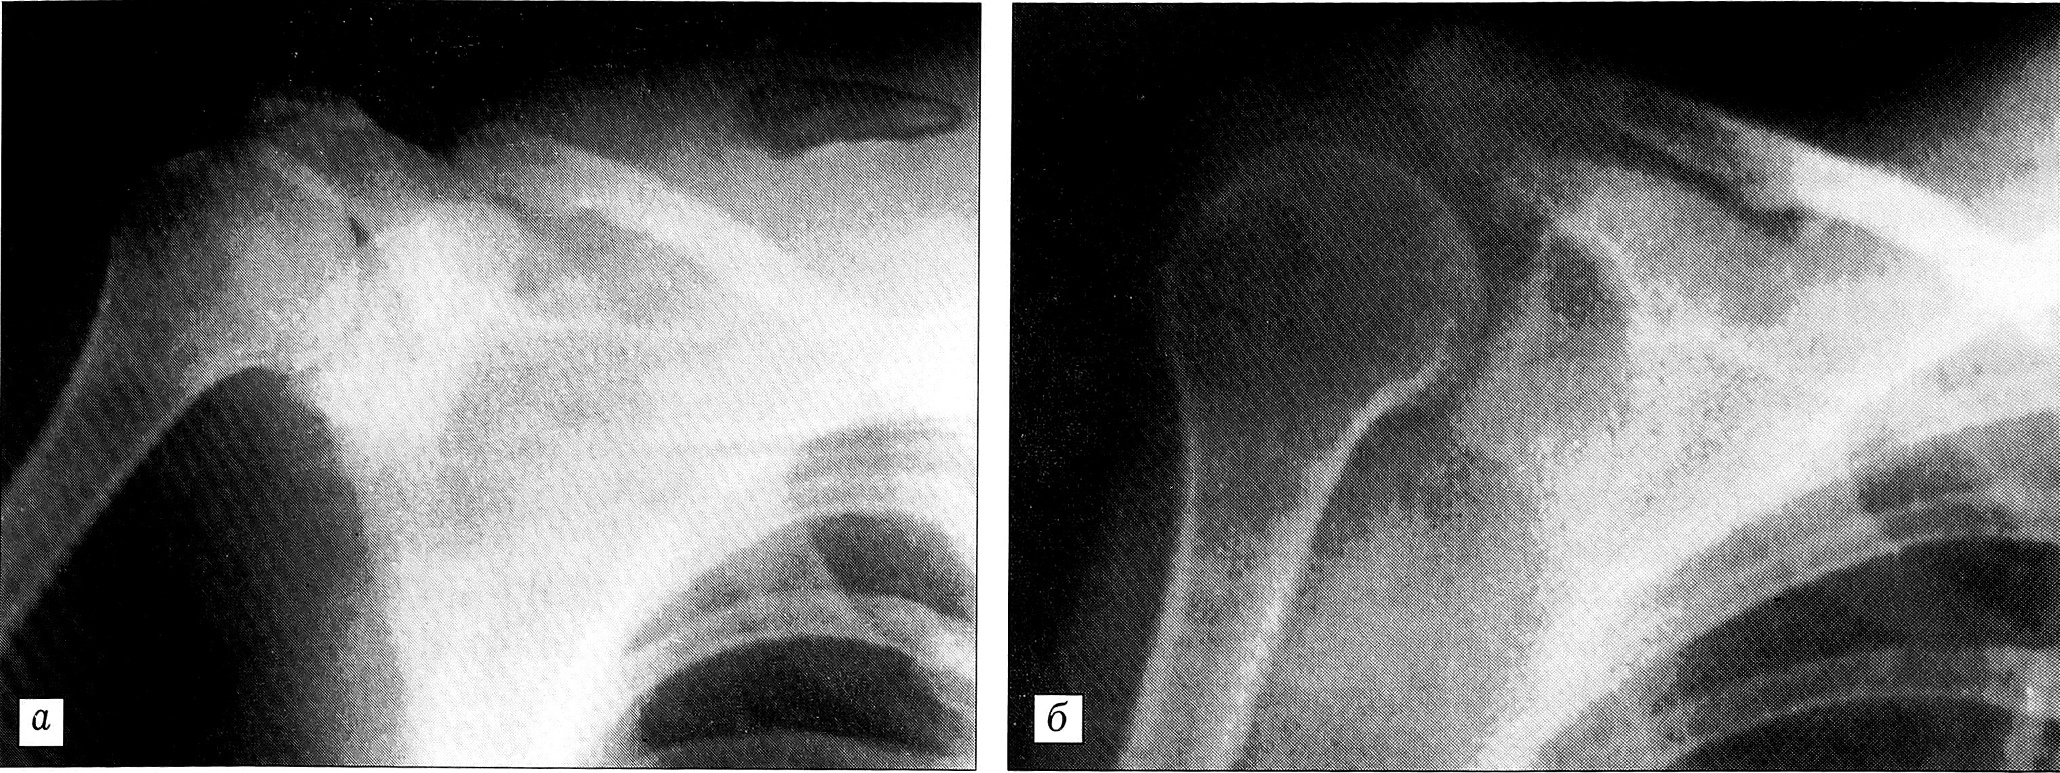

Рис. 1. Рентгенограммы больной Т. при поступлении (а) и через 8 мес после травмы (б).

Клиническое наблюдение. Больная Т.,20 лет, выпала из салона легкового автомобиля, который двигался с большой скоростью. Доставлена бригадой скорой медицинской помощи в тяжелом состоянии. Сознание — сопор. Пульс 118 в минуту. АД 60/30 мм рт. ст. При аускультации легких дыхание проводится во все отделы. Живот мягкий. На голове рана 12x4 см с отслоением кожи. В области правого плечевого сустава значительный отек, распространяющийся на надплечье, грудную клетку, плечо. Пульсация на плечевой, лучевой и локтевой артериях отсутствует. Кисть теплая. Активных движений в руке нет. Анализ крови: НЬ 89 г/л, эр. 2,5 • 1012/л, Ht 27%. Общий анализ мочи в норме. На краниограммах патологии не выявлено. На рентгенограммах грудной клетки и плечевого сустава справа обнаружены латеральное смещение лопатки, расширение щели акромиально-ключичного сустава до 3 см (рис. 1, а). При люмбальной пункции выявлена кровь в ликворе. Результат лапароцентеза отрицательный. Диагноз: ушиб головного мозга, субарахноидальное кровоизлияние, лопаточно-реберная диссоциация справа, разрыв акромиально-ключичного сочленения, плечевого сплетения, подключичной артерии и вены, мышц плечевого пояса, травматический шок III степени.

В амбулаторных условиях продолжались медикаментозная терапия, лечебная физкультура, массаж, физиотерапия. Однако грубые неврологические расстройства в руке и отсутствие пульсации на артериях плеча и предплечья сохранялись. Больная признана инвалидом II группы. Через 8 мес после автотравмы обратилась за помощью по поводу отморожения II степени потерявшей чувствительность руки. Сохранялись полный паралич руки, выраженная гипотрофия мышц, отсутствие пульсации на плечевой, лучевой и локтевой артериях. Парализованную руку предпочитала носить на косынке. На контрольных рентгенограммах исчезли латеральное смещение лопатки и диастаз между ключицей и акромионом. В области клювовидно-ключичной связки определяется оссификат (рис. 1, б).